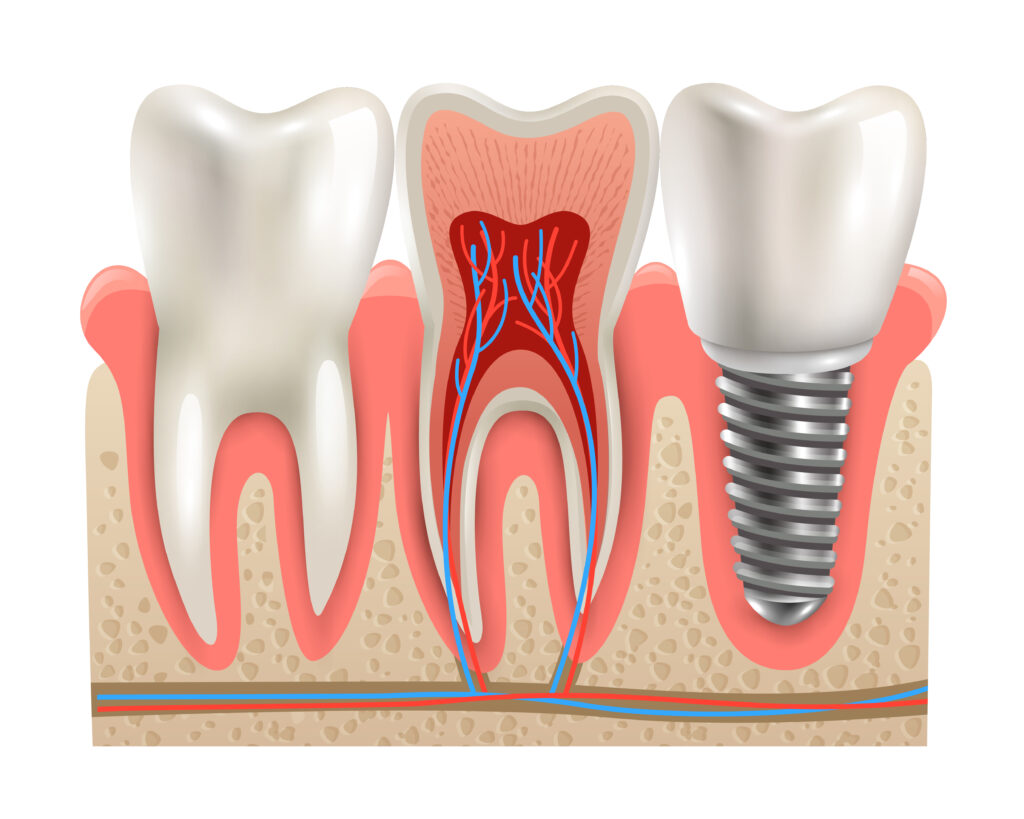

One of the most important advantages of dental implants in Vasant Kunj is that they replace both the visible portion of the tooth and the root beneath the gumline. Traditional treatments such as bridges or dentures typically replace only the crown of the tooth, leaving the underlying bone without stimulation.

A dental implant consists of a small titanium post that is surgically placed into the jawbone. Titanium is widely used in medical treatments because it is strong, biocompatible, and capable of bonding naturally with bone tissue. Over time, the implant integrates with the jawbone through a process called osseointegration.

Once this integration is complete, a custom dental crown is attached to the implant. The final result is a replacement tooth that looks, feels, and functions very similar to a natural tooth.

Because the implant becomes part of the jawbone structure, it provides excellent stability. Patients who choose dental implants in Vasant Kunj often find that their replacement teeth feel secure and natural when speaking or chewing.

Bone loss is one of the most serious long-term effects of missing teeth. When a tooth root is no longer present, the jawbone in that area gradually begins to shrink. Over time, this can lead to changes in facial structure and the weakening of surrounding teeth.

Dental implants address this issue by replacing the missing root and restoring stimulation to the jawbone. Each time a patient bites or chews, the implant transfers pressure to the bone, helping maintain its strength and density.